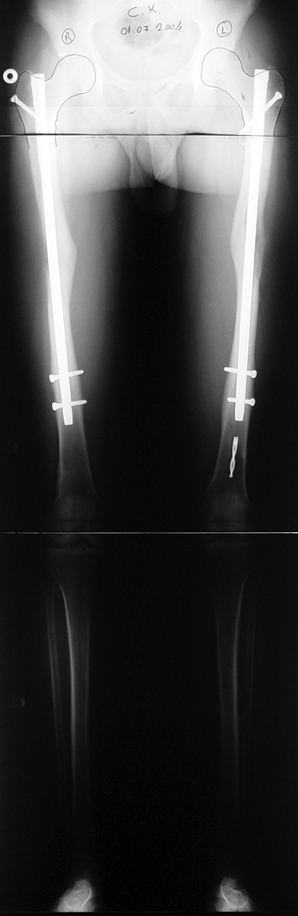

Biz son zamanlarda, seçilmiş vakalarda, uzatma sonrası uzunluğu ve “alignment’ı” korumak amacı ile unilateral dinamik aksiyel fiksatör ve kilitli intramedüller çivi kombinasyonunu tercih etmekteyiz. Bu yöntemin ön şartları medullanın en dar çapının 7 mm.’den geniş olması ve uzatma sonrası distalde en az 8 cm. uzunluğunda çivi kalabilmesidir. İntramedüller çivi hem uzatma esnasında femurun üzerine gelen makaslama ve bükülme kuvvetlerini nötralize etmekte hem eksternal fiksasyon süresini kısaltmakta, hem de yeni oluşan kemiği kırıklara karşı korumaktadır. Serimizde bir vakada subtrokanterik femoral osteotomi yapılmıştır. İntramedüller çiviye rağmen varus angulasyonu oluşması yönünde bir dezavantaj tespit etmedik.

İlizarov, distraksiyon osteogenezisi için endosteal kan dolaşımının önemini vurgulamıştır. Biz tüm vakalarımızda femuru oyarak intramedüller çiviyi çaktık; buna rağmen hiçbir vakada kallus oluşma süresi tahminimizden daha uzun olmadı. Bu yüzden medüller dolaşımın bozulmasına bağlı yeni kemik oluşma hızında bir yavaşlama olmadığını düşünüyoruz. Oyma sonrası meydana gelen revaskülarizasyon, intramedüller çivili fiksasyon stabilitesi ve erken fonksiyonel yüklenme bu gerçeğin temelini oluşturmaktadır. Eksternal ve internal fiksasyon yöntemlerinin kombine kullanımının potansiyel dezavantajları kan kaybının artması, intramedüller infeksiyon, yağ embolisi olasılığı ve aşırı metal yüküdür. Bunların içinde en çok korkulan problem bir çivi dibi infeksiyonun tetikleyeceği derin intramedüller infeksiyondur (panosteomyelit). Bizim serimizde bu yönde hiçbir komplikasyon gelişmemiştir. Bu olası komplikasyonun önlenmesi amacı ile uzatma sonundaki kilitleme medialden yapılmalıdır; ayrıca intramedüller çivi ve eksternal fiksasyon pinlerinin teması önlenmelidir.

İntramedüller çivi ve eksternal dinamik aksiyel fiksatör kombinasyonu teknik olarak standart İlizarov uygulamalarından daha zordur. Ancak şu avantajlar yöntemi cazip hale getirmektedir; eksternal fiksasyon süresinde kısalma, refraktüre karşı korunma, erken rehabilitasyon, azami hareket genişliği kazanma ve günlük yaşam konforu. Bu avantajlar artan maliyet , artan kan kaybı ve potansiyel derin infeksiyon gibi dezavantajların önüne geçmektedir. Sonuç olarak, bulgularımızın eşliğinde, intramedüller çivi üzerinden femoral uzatma tekniğinin güvenilir ve dayanıklı bir metod olduğunu ve bizce standart İlizarov uygulamalarına üstünlük sağlayan avantajlar getirdiğini söyleyebiliriz.